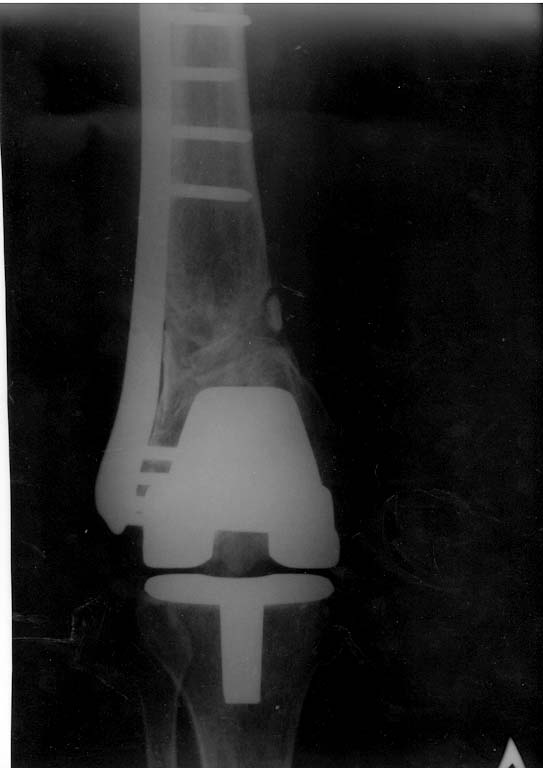

Добрый день. Оперировать не рекомендовали. После 3-х лет после операции- вот такая картина. Прокомментируйте пожалуйста снимки.

В предыдущем сообщении к сожалению не удалось прикрепипь все снимки.Сейчас это исправляю.Высылаю все снимки в хронологии.

Прошу Вас прокомментировать динамику. Почему пластина опустилась? И наблюдается ли все-таки сращение?

Снимок только в одной проекции, для более полной оценки ситуации надо и фас увидеть. И в первую очередь узнать о клиническом статусе - жалобы, ось, длина, амплитуда движений в колене, опоросопособность, потребность в дополнительной опоре?